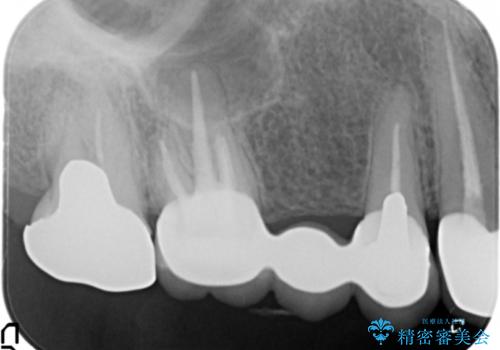

- 被せ物と歯ぐきの境目が黒いことを気にされ、来院された患者様です。

精査したところ、メタルボンドクラウンの金属部分が露出し黒く見えていました。

患者様のご希望により、金属を使わないオールセラミックのブリッジによる補綴治療を行いました。

金属の土台も除去し、ファイバーコア(金属を使わない強度のあるしなやかな土台)へやりかえました。